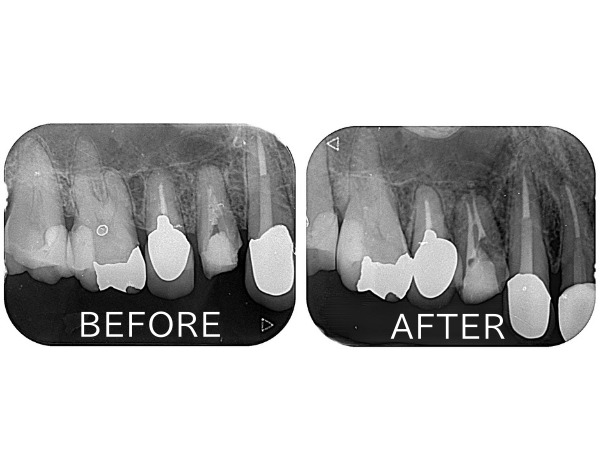

こちらが術前のレントゲン写真になります。

右上の前から4番目(第一小臼歯)の歯が治療途中の状態でした。レントゲン写真から根の中に詰める材料が根の先まで到達しておらず、根の先の骨が溶けている状態であることが分かりました。原因は根の中がしっかり清掃されない状態で不十分な材料の充填となってしまったため、根の中で細菌が繁殖してしまっているためです。

こちらが術後のレントゲン写真になります。

メインの2つの根管だけでなく、間にある側枝と呼ばれる通路にまでお薬が入ったことがわかります。

患者様は「噛むと痛い」という術前の症状が消えました。またレントゲンで根の先にあった黒い影も改善傾向を認めてきています。